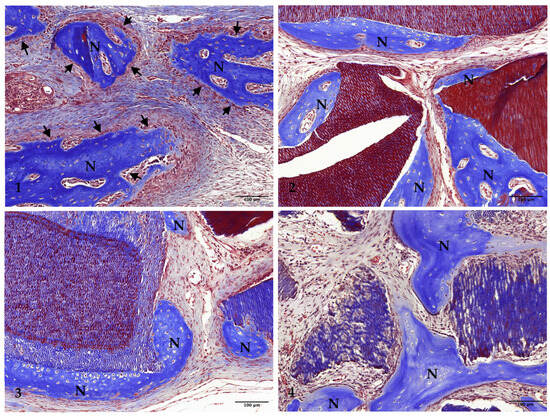

3.1. Histological Analysis

3.2. Two-Week Results

3.3. Four-Week Results

3.4. Eight-Week Results